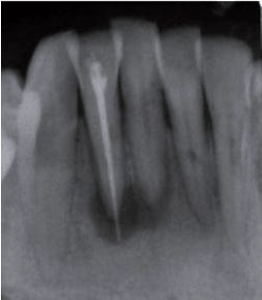

INSTRUÇÃO: A questão é baseada no caso clínico e radiografia abaixo.

Paciente do gênero feminino, 33 anos, procurou atendimento odontológico queixando-se de dor há algum tempo no dente 42 durante a mastigação. Relatou que tinha feito endodontia no dente em questão havia alguns meses. Ao exame radiográfico, verificou-se presença de área radiolúcida no terço apical dos dentes 41 e 42 e sobreobturação no 42. O dente 41 respondeu negativamente ao teste de vitalidade.

Qual o tratamento mais indicado?